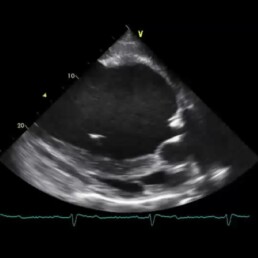

- Darstellung des Herzens (in verschiedenen Ebenen) und des Blutflusses

- nicht vollständig schließende Aortenklappe sichtbar

- pathologische Verwirbelungen des Blutflusses

- nach Messung Vergrößerung der linken Herzkammer